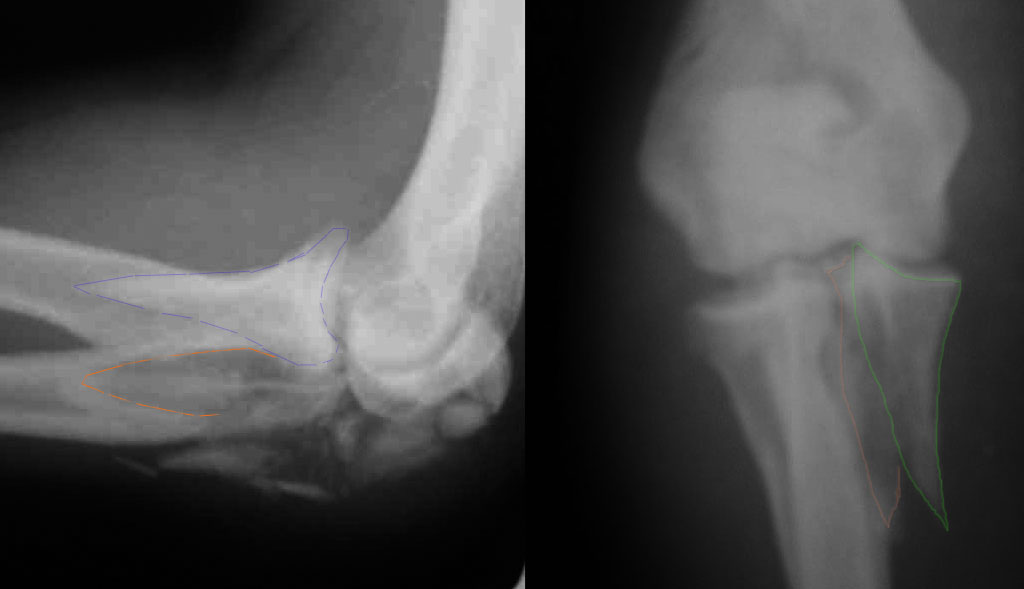

При самом большом к Вам уважении, Сергей Анатольевич, не соглашусь. У меня, после того, как добавили "прямой" снимок, сомнений не осталось. Венечный сломан наверняка. Но чтобы судить, насколько это критично для стабильности, нужно иметь строго боковую проекцию. И при этом помнить, что на него крепятся медиальные связки.

Прикрепляю снимок, где обведен фрагмент, несущий на себе венечный отросток (весь он смещён с этим фрагментом или частично - без качественной боковой проекции судить сложно), и отдельно на снимке обведено "ложе", от которого он сместился.

Почему я в данном случае против Вебера (хотя обычно горячий сторонник)? Да потому, что спицам нередко не хватает жёсткости, чтобы удержать предплечье от волярного подвывиха. При таком оскольчатом переломе спицы порой просто "прогибаются" за счёт одного только натяжения проволочной петли и головка луча может уйти в волярный подвывих (может, конечно, и не уйти). Но я бы предпочёл фиксировать всё к жёсткой пластине (включая фрагмент с венечным отростком) и, по возможности, исключить послеоперационную внешнюю иммобилизацию. Накладывать на такой локоть после операции гипс -- означает обрекать его на тяжёлую контрактуру.

Головка луча, кстати, на мой взгляд цела.